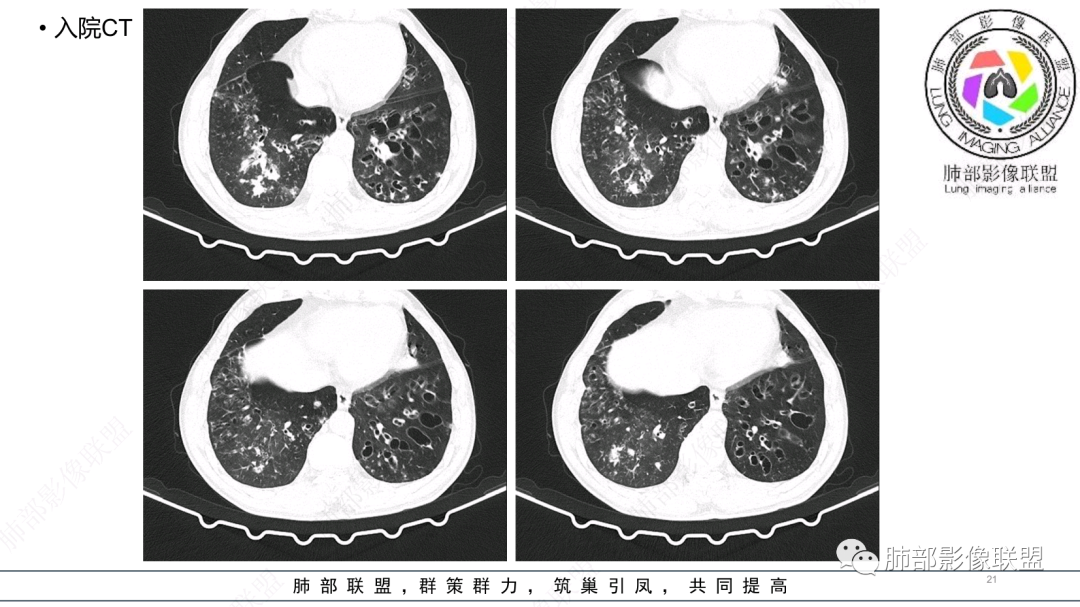

中老年男性,发病一周,发热,炎症指标明显增高,双肺支气管扩张基础,双肺可见多发结节、斑片状、团块状密度增高,边缘尚清。病灶分布与支气管关系密切,考虑支扩合并感染,铜绿,NTM、奴卡、曲霉等,环卫工人,可能接触腐败物较多,考虑曲霉可能大,鉴别奴卡。

男性,56岁,清洁工,临床表现咳嗽咳痰发热。胸部影像:两肺散在斑片、结节及实变影,大部分沿气道分布,以下肺为著并伴发多发支气管扩张及囊腔影,实验室检查白细胞增高,考虑感染性病变,曲霉、铜绿及NTM。

56岁,工作性质:环卫工人。主诉:咳、痰、喘、发病一周。急性起病(或者慢病+AE),呼吸道感染症状。化验指标白细胞、中性、CRP明显升高。影像学显示多灶性,有柱状支扩,囊状支扩等结构肺病,责任细菌主要考虑铜绿假单胞菌,不排除合并其他细菌以阴杆为主;存在树芽影,发热,炎症沿支气管束分布,是否合并TB?真菌?;树芽伴发热支原体感染也要需要考虑进去;全肺多灶性炎症,部分病灶周围有晕,右上叶疑似反晕,内部疑似有丝,右下肺考虑存在粘液栓,加之环卫工工作性质,考虑霉菌,主要考虑曲霉。

两肺支扩,两肺沿支气管分布多发结节、树芽及团块,边缘模糊,部分支气管管壁增厚,考虑气道侵袭性曲霉菌,鉴别铜绿、奴卡、结核。

大部分树芽比较模糊。

支气管壁增厚,晕征明显,病灶沿着支气管纵向分布,结合患者职业,考虑气道侵袭性曲霉。

多发结节,部分结节边缘清楚,部分边缘模糊,支扩合并肉芽肿性炎,奴卡菌与曲霉之间选择。